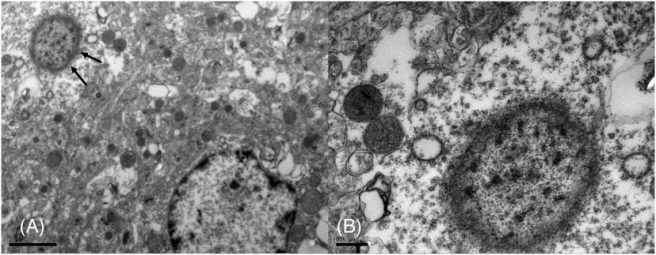

But most interesting of all, they also observed “widely distributed variably sized (up to ~100 μm in diameter), round to elongate, well-defined eosinophilic structures“. They did not refer to them as Lewy bodies, but rather Lewy body-like inclusions.

Now, it should be noted that the researchers looking at the brains of the poor parrots described what they observed in the brains as Lewy body-like inclusions. Firstly, the structures that they observed were 2-3 times larger than your typical Lewy body. In addition, they lacked a distinctive core and did not display the normal halo of Lewy bodies.

But they did contain alpha synuclein protein.

Another feature of the brains was changes in the shape of the neurons. The neurons containing one of these Lewy body-like inclusions, the investigators noted that enlargement of the cell body, displacement of the nucleus towards the side of the cell, and a smaller than normal nucleus. This could be considered a sign of a cell under a great deal of stress, and perhaps in the early stages of cell death. To reinforce this view, the investigators also reported that some of these neurons were partially engulfed by glial cells, suggesting that the cells were in serious trouble.